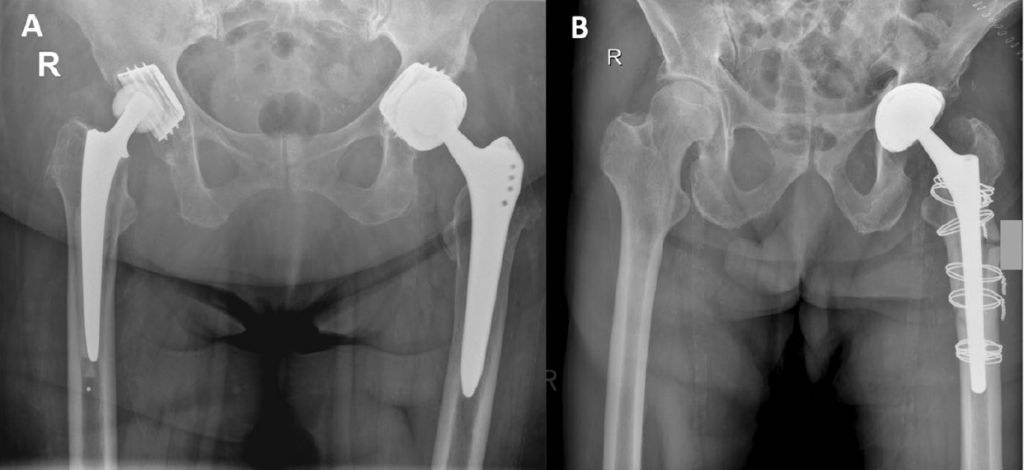

Die Hüft-Totalendoprothese ist ein künstlicher Ersatz des Hüftgelenks, das aus einer Pfannenkomponente (Acetabulum) und einer Schaftkomponente besteht, die in den Oberschenkelknochen eingesetzt wird (Mikkelsen et al., 2014). Die Hauptursache für eine notwendige Hüft-TEP ist die Arthrose, bei der der Knorpelverschleiß zu starken Schmerzen und Bewegungseinschränkungen führt (Siebert, 2017). Weitere Indikationen sind Frakturen des Oberschenkelhalses oder entzündliche Gelenkerkrankungen wie rheumatoide Arthritis (CJRR, 2022).

Die Wahl der Prothesenmaterialien spielt eine entscheidende Rolle für die Langlebigkeit und Funktion der Hüft-TEP. Häufig verwendete Materialien sind Metall-Polyethylen-Kombinationen oder hochentwickelte Keramikgelenke, die eine höhere Abriebfestigkeit und bessere Biokompatibilität aufweisen (Siebert, 2017).